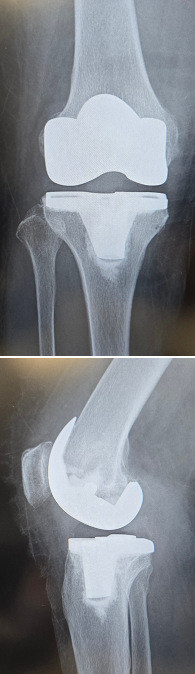

当院にて両側の人工ひざ関節全置換術(TKA)を施行。

高度のO脚変形があり、歩行時のひざの不安定感も強い症例です。

キネマティックアライメント法で手術を行いました。

キネマティックアライメントとは、ひざ本来の靭帯のバランス、下肢の形を取り戻すことに重点を置いた方法です。

〈手術前のレントゲン〉

〈手術後のレントゲン〉